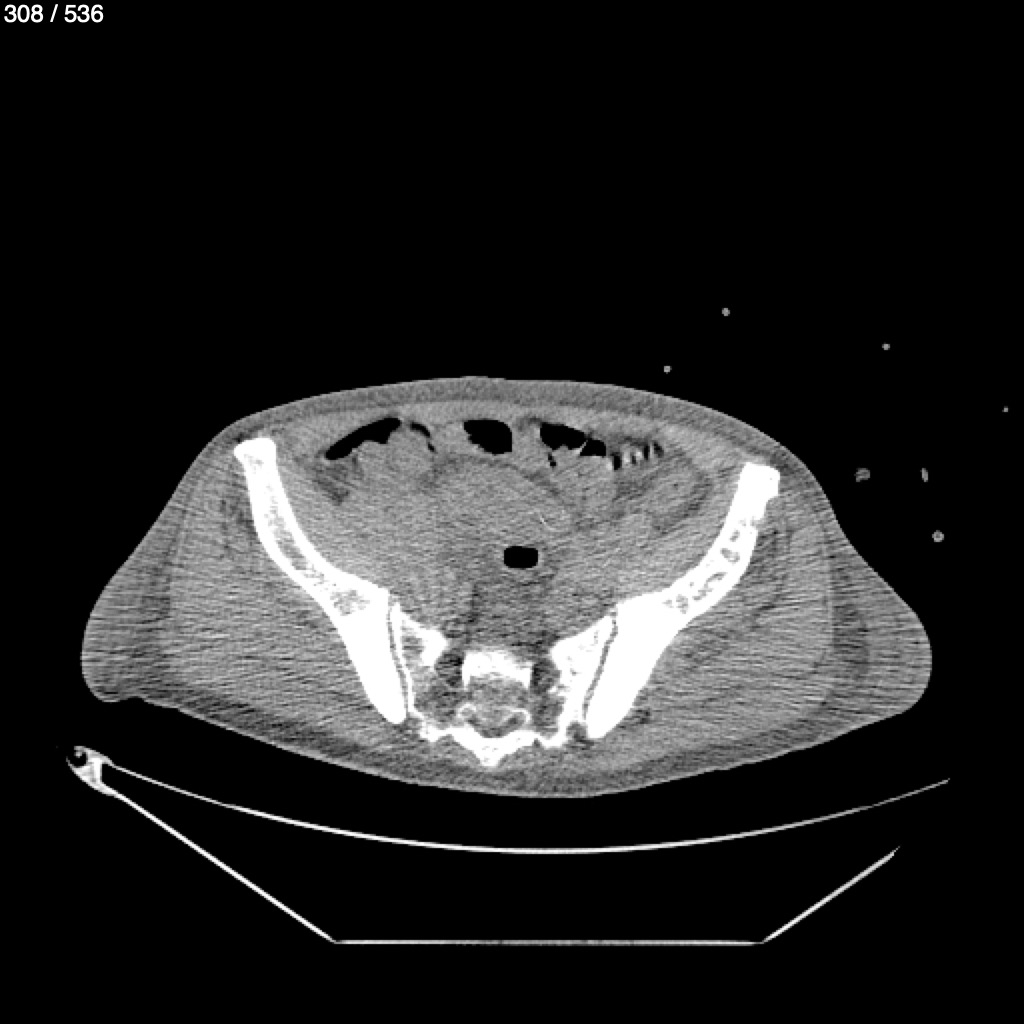

Angel Villalobos Palomeque 73 A - T.C Abdomen Simple